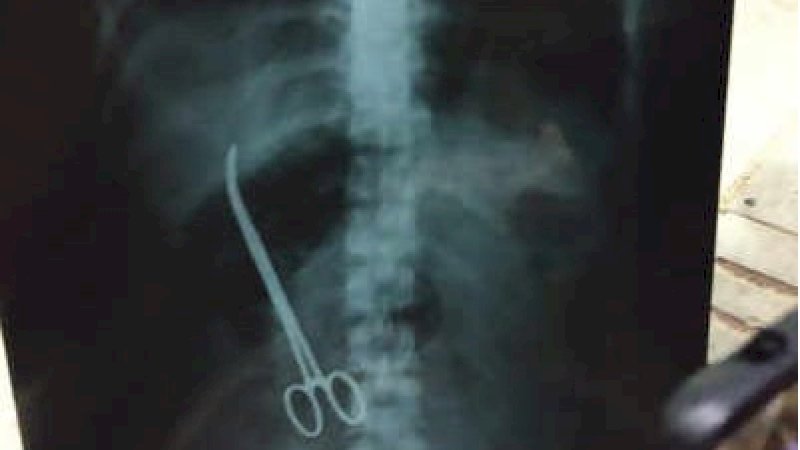

RAKYATKU.COM - Maheshwari Chowdhary (33) mengerang kesakitan usai menjalani operasi hernia. Awalnya dikira pengaruh usai operasi. Namun, hasil rontgen menampakkan ada gunting yang tertinggal di dalam perut wanita ini.

Hampir tiga bulan lamanya gunting medis itu berada dalam tubuh Maheshwari Chowdhary. Ia dioperasi pada 1 November di rumah sakit Hyderabad, India.

“Dia telah mengeluh sakit perut yang parah pada waktu tetapi kami pikir itu karena operasi. Ketika dia dibawa ke rumah sakit kemarin, laporan rontgen jelas menunjukkan gunting. Awalnya, otoritas rumah sakit enggan memberi kami sinar-X tetapi kami berhasil mendapatkannya, ”kata kerabat pasien, Mahadev.